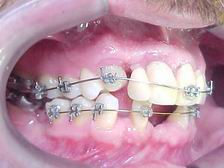

Evolução no nivelamento do canino

Lado oposto